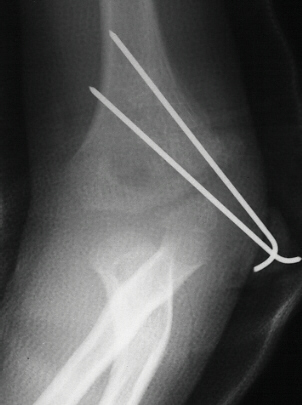

- XRAYS: Radiographic examination of the right upper extremity revealed

a displaced fracture involving the lateral condylar physis exiting through

the substance of the capitellum.

- TREATMENT: The patient was taken to the operating room where under

general anesthesia and tourniquet control the fracture was exposed utilizing

an anterolateral approach, taking care not to disturb the posterior vascular

pedicle of the lateral condyle. Following adequate reduction of the fracture,

2 diverging k-wires were placed across the fracture site.

The

patient was immobilized in a long arm cast at 90 degrees until radiographic

evidence of healing was apparent. The long arm cast and k-wires were removed

in clinic.